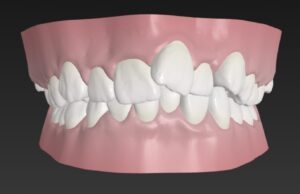

🔶初診時🔶

正面

でっ歯さん

歯並びガタガタのそうせいを気にして

マウスピース矯正希望で来院